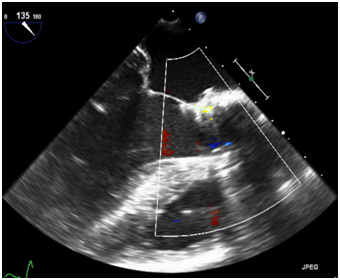

79 y old male patient, known to have diabetes mellitus, end stage renal failure and chronic obstructive pulmonary disease, this patient had aortic valve replacement (AVR) 15years prior, but because of infective endocarditis 7years ago, he underwent a redo AVR (Aortic valve Bioprosthesis) using a 25mm cry preserved aortic homograft implanted as a full root in another hospital. Patient was admitted with severe heart failure and pulmonary edema. His Echocardiogram showed severe AR (Figure 1). Patient was treated aggressively with anti-failure medications. The case discussed in heart team and both options AVR vs TAVI were raised in this high risk patient, with STS score 18. Both the heart team and Family preferred TAVI, According to sizing application this homograft valve will fit with Size 29mm Core Valve, The CT-scan measurements showed an aortic annulus size 21-25mm at different level, Perimeter range from 71-73, 3mm, Aortic valve area 2.9 cm2, and a heavily calcified a tube-like aorta (Figure 2). No clear sinus or junction was seen by CT. A trans-femoral approach for Valve in Valve was used. A 29 mm Medtronic Core valve was deployed and the landmark was the calcium in the root. Unfortunately, it migrated up-ward most probably due to the rigidity of the homograft tube and no real narrowing or calcified leaflet to anchored the valve (Figure 3). Therefore we used another 29 core valve and deployed it through the first one which was well seated in ascending aorta as support. This method of support was very successful for final deployment (Figure 4). It was similar to the melody valve deployment in treating pulmonary regurgitation. There was no aortic regurgitation by Echocardiogram (Figure 5). Patient was very stable and discharged home after 48hours.

Figure 2 Ct-scan image of ascending aorta with heavy calcification and full root replacement.